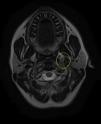

Based on the clinical presentation, the patient was diagnosed with a painful left-sided, partial Horner syndrome of unknown etiology based on the anisocoria and ptosis OS findings, however carotid artery dissection was highly suspected given the painful nature of presentation. Emergent imaging studies (including MRI/MRA, chest X-ray, and CT scans) were arranged through the PCP that same day. Four days later the PCP notified our clinic that the imaging studies had, indeed, revealed a carotid artery dissection of the distal half of the left internal carotid artery (ICA) at the level of approximately cervical vertebrae C3. Figs. 2–4 highlight the dissection of1 the left internal carotid artery via standard MRI and MRA which was classified as “severe” by the radiologist and scored as an “8 or 9 on a scale to 10”. The PCP had urgently started the patient on 325mg of aspirin daily and referred the patient to a neurologist for further consultation.